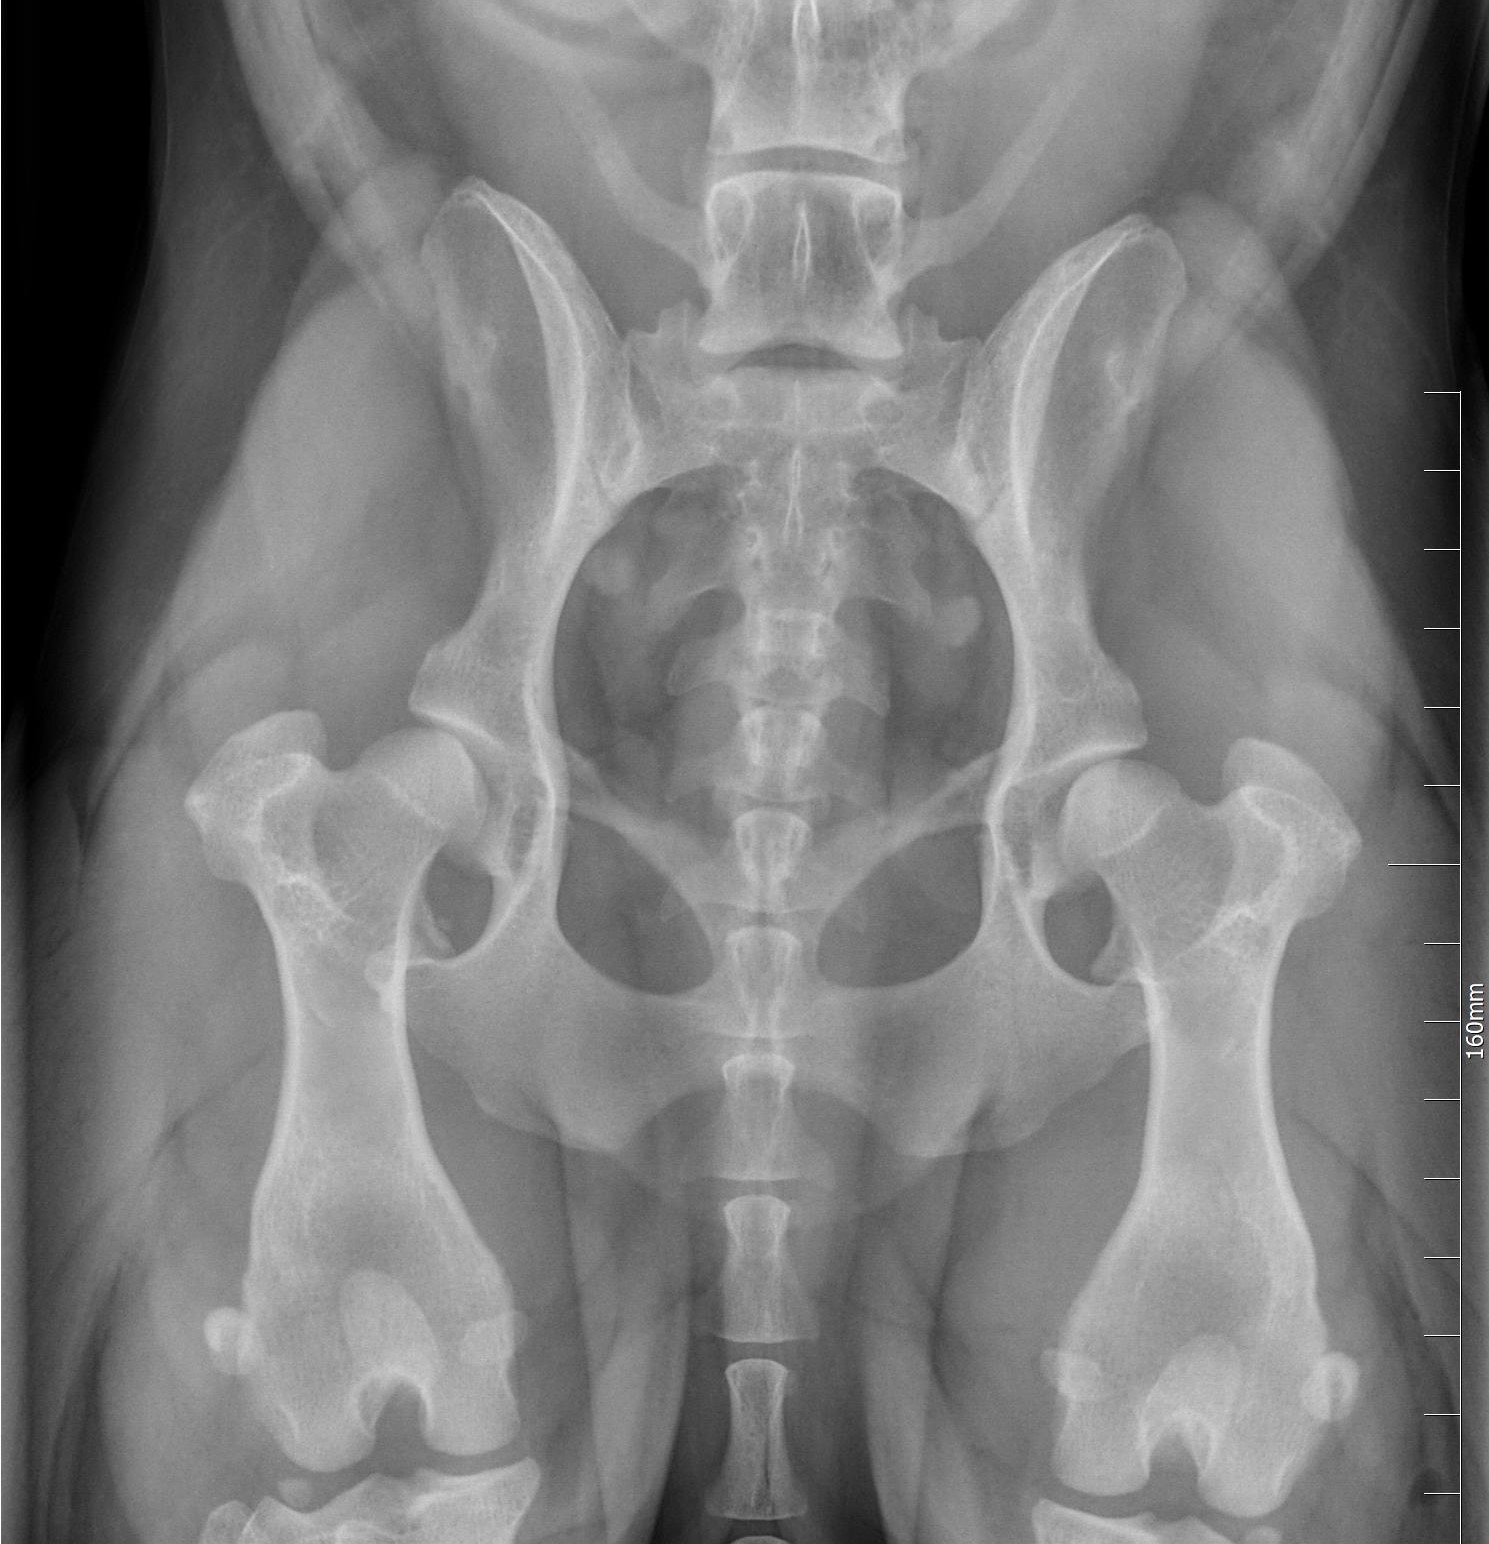

LONKKANIVELEN KASVUHÄIRIÖ

Lonkkanivelen kasvuhäiriö eli "lonkkavika", (engl. hip dysplasia, HD) on koirien yleisin luuston ja nivelten kasvuhäiriö. Se voidaan määritellä perinnölliseksi lonkkanivelen löysyydeksi. Lonkat ovat syntymähetkellä silmämääräisesti normaalit, mutta muutokset alkavat jo pennun ensimmäisten elinviikkojen aikana.

Löysyys lonkkanivelessä johtaa reisiluun pään ja lonkkamaljan riittämättömään kontaktiin. Alueelle kohdistuu epänormaalin suuri paine, joka on sitä suurempi mitä pienempi kontaktialue on. Tämä voi johtaa mikromurtumiin ja lonkkamaljan mataloitumiseen. Noin vuoden iässä lantion luutuminen on täydellistä ja yleensä kipukin helpottaa tässä iässä.

Lonkkanivelen kasvuhäiriö johtaa usein nivelrikkoon. Nivelrikon kehittymisen aikatauluun ja tyyppiin vaikuttavat rotukohtaiset ja yksilölliset erot. Lonkkanivelen kasvuhäiriön perimmäistä syytä ei tiedetä, mutta se periytyy tämänhetkisen tutkimustiedon perusteella kvantitatiivisesti eli siihen vaikuttaa useita eri geenejä. Myös ympäristöllä on vaikutusta lonkkavian ilmenemiseen ja vaikeusasteeseen.

Corgeilla on lonkkanivelen kasvuhäiriöitä lievästä - vaikea asteiseen. Ylipaino vain pahentaa oireita ja tämä on yksi niistä syistä, miksi cardigania ei tule päästää liian lihavaan kuntoon!